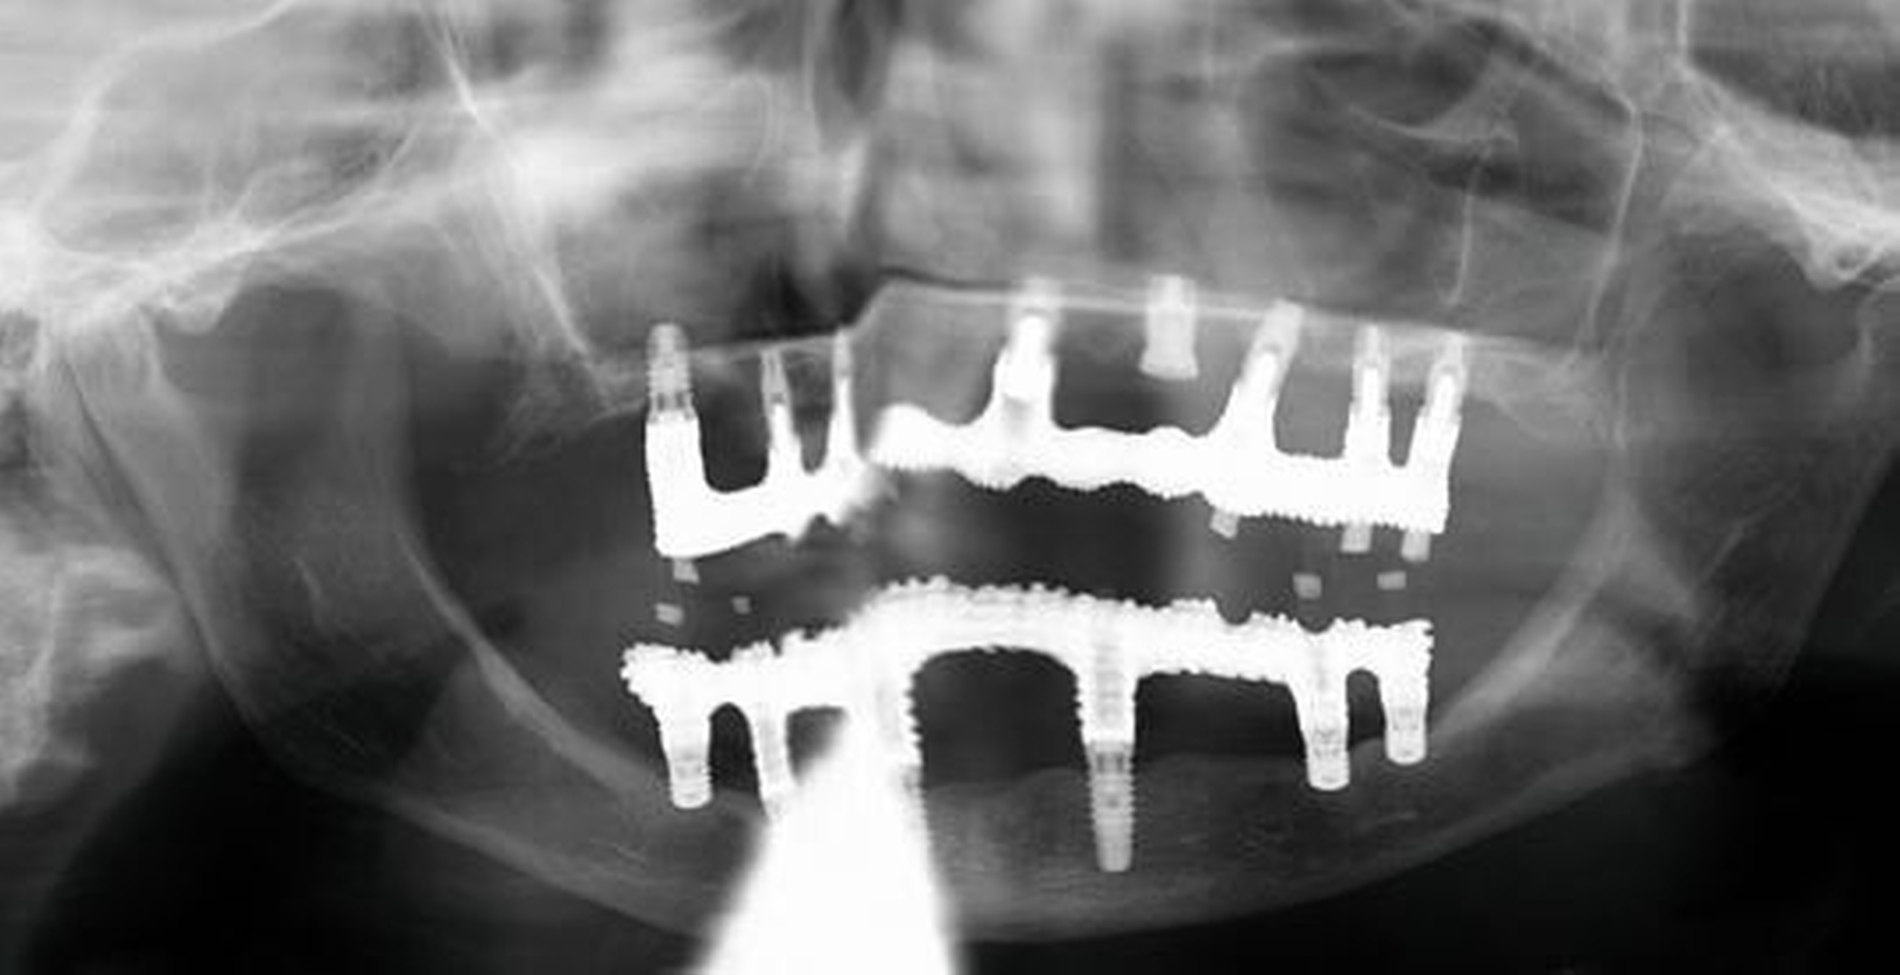

Zahnmedizinische Leitlinien zur zahnmedizinischen Betreuung von geriatrischen und demenziell erkrankten PatientInnen sind aktuell im Entstehungsprozess. Zusätzlich zu den oft komplexen zahnmedizinischen Befunden müssen bei der individuellen Therapieplanung dieser vulnerablen Klientel die Therapiefähigkeit und die Eigenverantwortlichkeit berücksichtigt werden. Dabei ist es weniger das Alter, sondern vielmehr der Zustand der körperlichen und mentalen Funktionsfähigkeit, der den Erfolg zahnmedizinischer Therapien limitiert. Therapien, die bei gesunden Personen jahrelang das Alltagsgeschäft der Zahnmedizin waren, sind bei Personen mit erhöhtem Pflege- und/oder Unterstützungsbedarf eventuell nicht umsetzbar. Gebrechlichkeit (Frailty) ist ein Zustand zwischen guter Gesundheit und Pflegebedürftigkeit im Alter – ein Zwischenstadium, in dem ein vorher fitter älterer Mensch Symptome der Gebrechlichkeit entwickelt und die Gefahr besteht, dass sich sein Zustand verschlechtert. Die geriatrischen Erkrankungen Frailty und auch Demenz sind im Rahmen zahnmedizinischer Behandlungen mit einer reduzierten Kooperations- und Therapiefähigkeit sowie bei der Anfertigung von Zahnersatz mit einer reduzierten Adaptationsfähigkeit assoziiert (Abbildung 3).

Patientinnen und Patienten mit stark reduzierter Therapiefähigkeit profitieren in besonderem Maß von zeiteffektiven Methoden und Materialien, zum Beispiel Bulk-fill-Kompositen, Reparaturfüllungen, Glasionomerzementen oder Intraoralscans. Die Therapiefähigkeit kann – ähnlich wie in der Kinderzahnmedizin – durch ein vertrauensvolles Verhältnis optimiert werden. Anders als in der Kinderzahnmedizin gibt es in der Alterszahnmedizin aber keine altersassoziierten Kontraindikationen für zahnmedizinische Interventionen. Voraussagbare Therapieergebnisse sind von besonderer Bedeutung, um erneute Behandlungen zu vermeiden. Das gesamte Spektrum zahnmedizinischer Interventionen kann bei der Behandlung von Personen mit Pflegebedarf sinnvoll sein. Die Abbildungen 6 bis 9 zeigen zahnmedizinische Interventionen bei Personen mit ausgeprägter Frailty (Stufe 7 der klinischen Frailty-Skala).